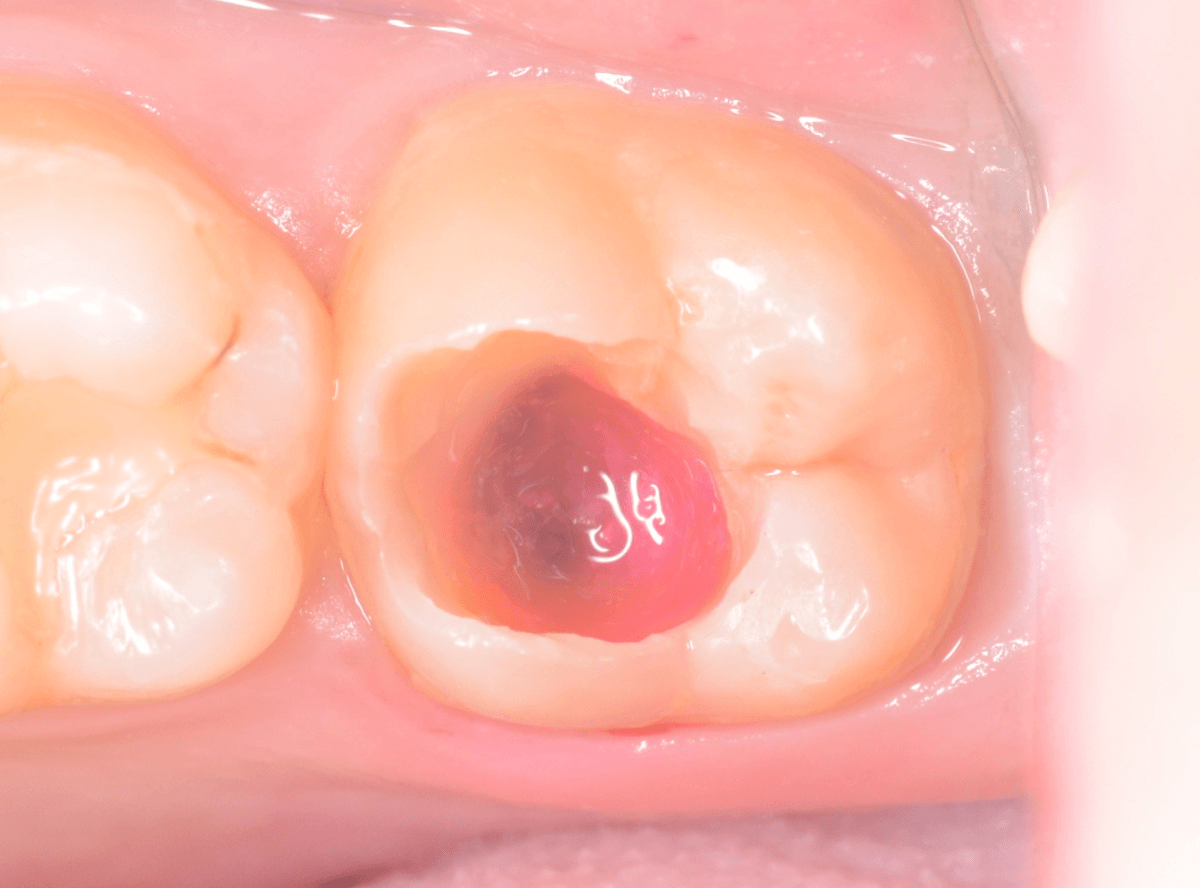

Case.14 CR(コンポジット・レジン)の下の深い虫歯

奥歯で咬んだ時に、痛みを感じるという訴えで来院された患者さんです。

パッと見は特に問題なさそうな状態ですが、大きなレジン治療がしてあり、レジンの奥もボヤっと黒っぽく見えてアヤシイ感じです。

麻酔をして、治療を開始します。

レジンを外すと、中から出血してきました。

これは、歯のスキマに歯肉が入り込んでしまったために起こってしまったものです。

おそらく、随分前から虫歯が進行していたと思われます。

止血しながら、電気メスで歯の中に入り込んだ歯肉を除去します。

虫歯と入り込んだ歯肉でぐちゃぐちゃになっている状態でした。

これでは、痛みが出てもおかしくありません。

慎重に全ての虫歯を除去したところです。

〇部が神経の入り口が見えているところです。

神経を保護する処置をして、しばらく経過観察しますが、痛みが出て神経を除去する必要が出る可能性も高いです。

痛みが出ませんように・・・。